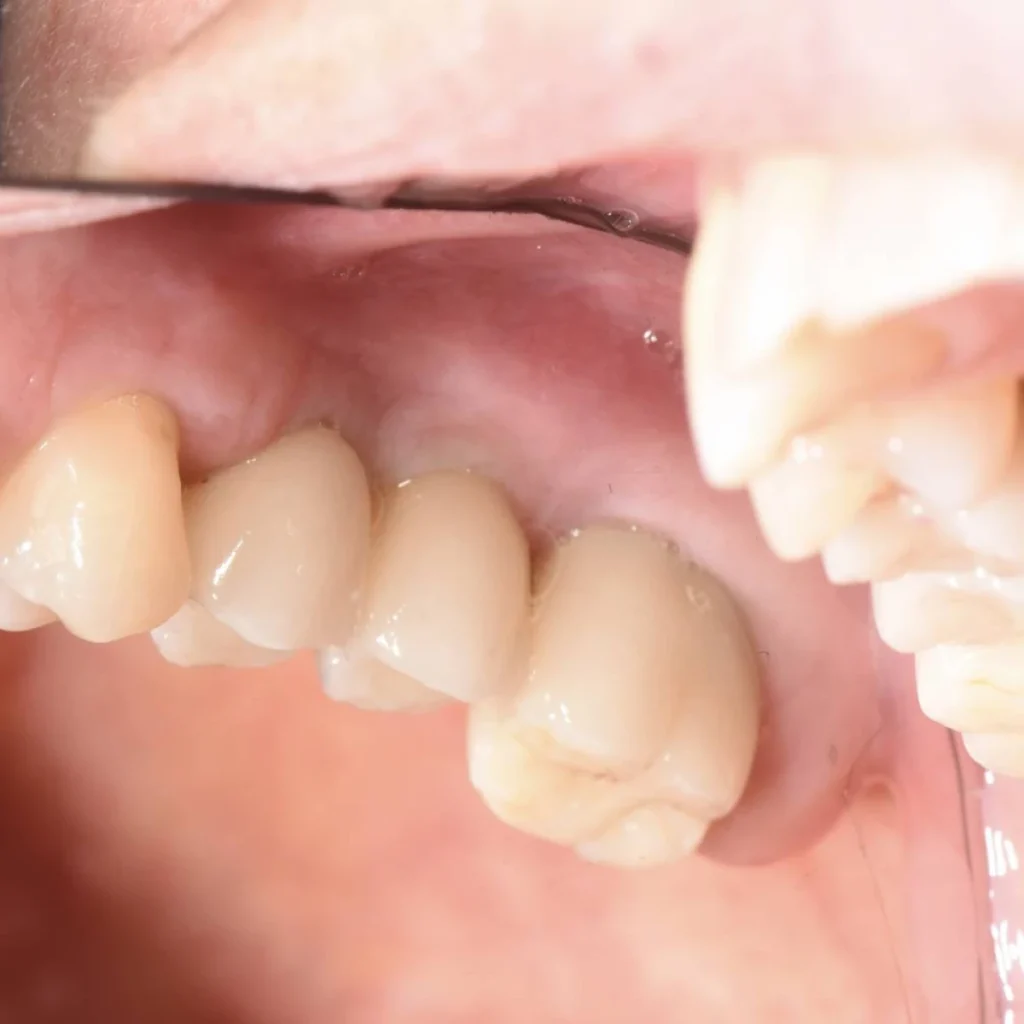

- Des couronnes tout céramique sont ensuite fixés aux implants.